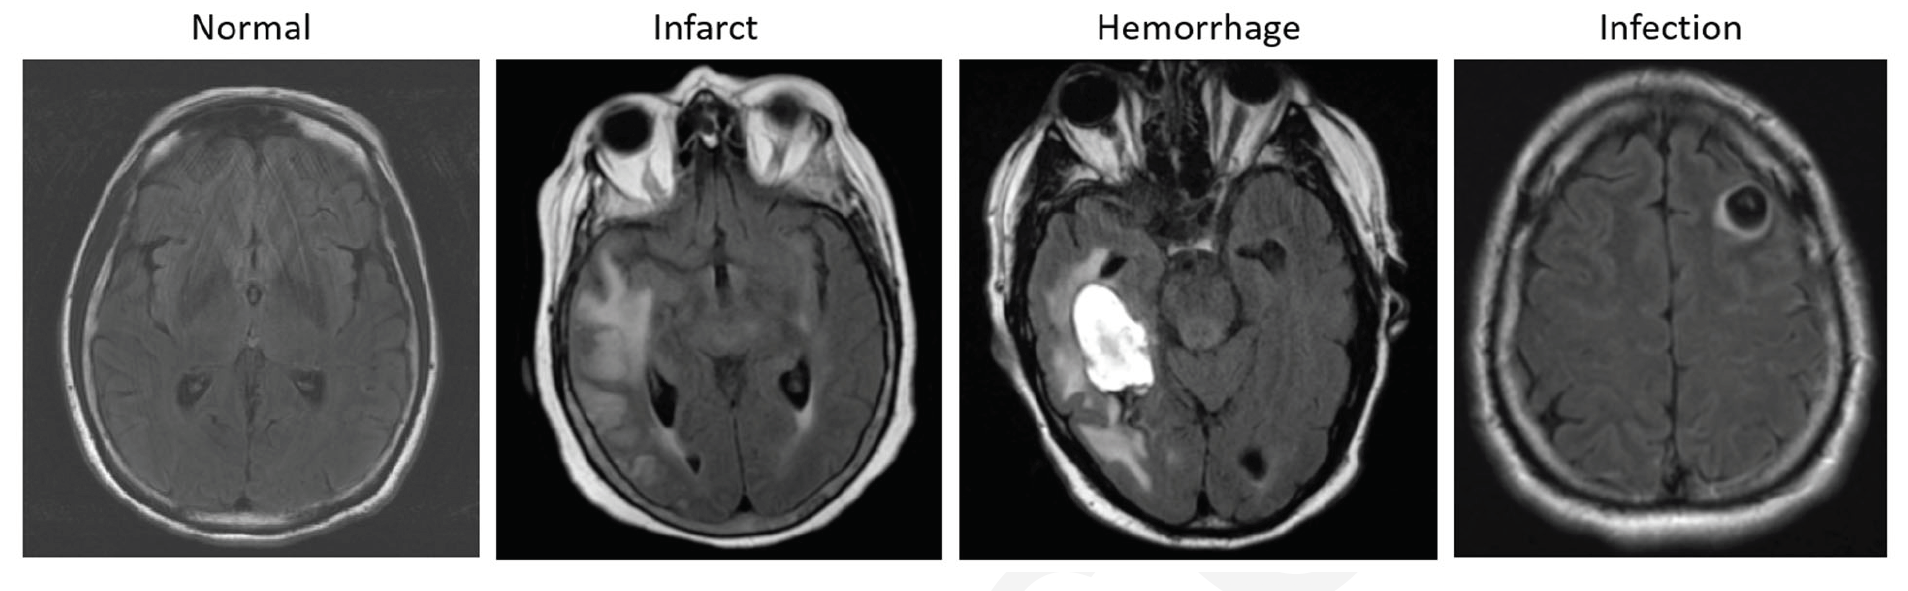

Examples of axial FLAIR sequences from studies within dataset A. From left

to right: a patient with a ‘likely normal’ brain; a patient presenting an intraparenchymal

hemorrhage within the right temporal lobe; a patient presenting an acute infarct of the

inferior division of the right middle cerebral artery; and a patient with known

neurocysticercosis presenting a rounded cystic lesion in the left middle frontal gyrus.

Credit: RSNA

For their retrospective study, the team used three large datasets that included more than 9,000 brain MRI scans culled from various institutions across two continents. They randomly split these datasets into training, validation, and test sets. All images were annotated by four radiologists who collated the studies into 10 categories: likely normal, almost normal, neoplasm, hemorrhage, infarct, infection or inflammatory disease, demyelination disease, vascular lesions, congenital, and other. In addition, FLAIR sequences were reviewed and categorized as “likely normal” and “likely abnormal.”